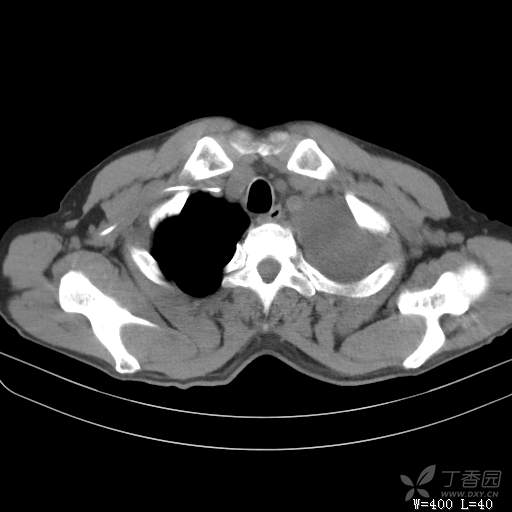

简要病史:胸闷、憋气伴低热1月

体格检查:T:37.6℃;P:92次/分;R:20次/分;Bp:100/60mmHg,神清,呼吸平稳,周身未触及肿大淋巴结,右肺及左上肺叩诊清音,左下肺叩诊浊音,右肺及左上肺呼吸音粗,左下肺未闻及呼吸音,心率92次/分,律齐,无杂音。腹部平坦,软,全腹无压痛,无反跳痛及肌紧张,肝脾肋下未触及,双下肢无水肿。

辅助检查:白细胞数目4.41 × 10^9/L,中性粒细胞百分比82.1%,*血红蛋白111g/L,*血小板数目91 × 10^9/L,凝血四项:凝血酶原时间12.5秒,国际标准化比值1.07,活化部分凝血酶原时间36.1秒,纤维蛋白原浓度6.52g/L,肾功能示:肌酐47.4umol/L,尿酸150umol/L,电解质示:钠133.5mmol/L,D-二聚体0.88mg/L,血沉67.71MM/H,C-反应蛋白114.6mg/L,肝功能:*总蛋白49.6g/L,*白蛋白27.4g/L,查胸水常规及胸水生化提示渗出液,胸水ADA154U/L,查胸水病理未见肿瘤细胞。超声:腹膜后有3~4枚肿大淋巴结,直径1~1.5厘米,余浅表淋巴结不大。

临床诊断:左侧胸腔积液